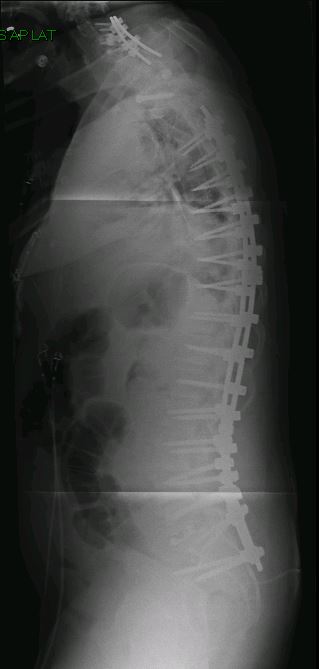

Imaging Gallery

Before & After

Spine Surgery

All imaging is fully de-identified. Patient identifiers removed in compliance with HIPAA.